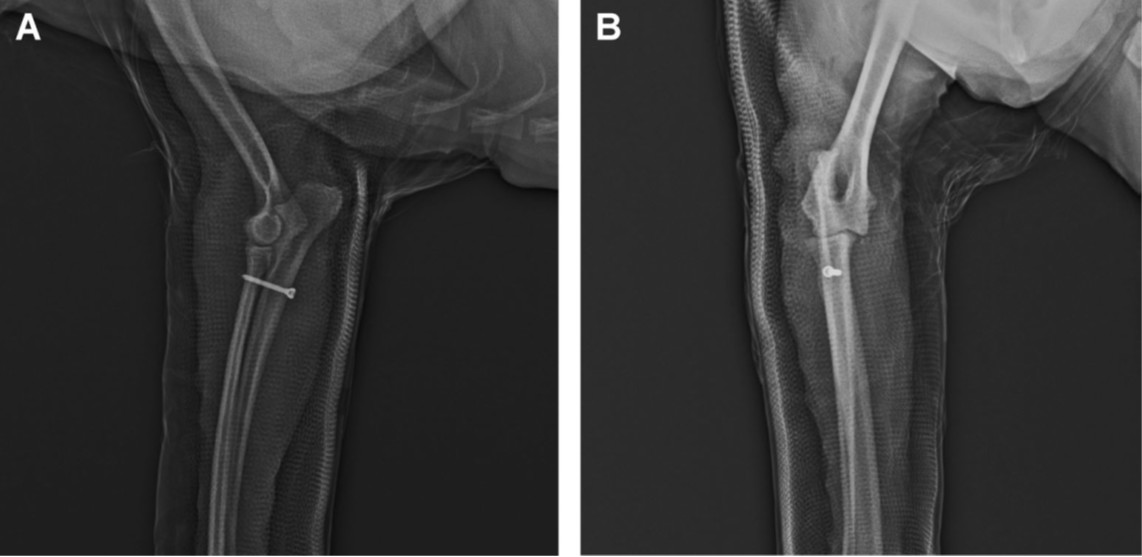

随后使用2-0不可吸收单丝缝线进行了切口缝合。术后X光片确认了桡骨头和肱尺关节的解剖复位,以及植入物的正确位置(下图)。肘关节通过夹板固定在伸展位,进行了10天的外部固定。

↑ 犬右前臂的正侧位(A)和头尾位(B)X光片,显示使用皮质螺钉进行术后肘关节脱位的复位情况。

术后第10天,拆除了绷带和缝线。进行了术后X光,未发现再次脱位的迹象。但犬仍然无法完全负重。

术后1个月,根据临床和X光检查,犬能够完全负重,关节活动范围正常,X光片上未观察到任何并发症。